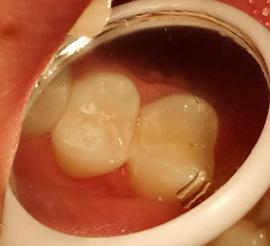

如果牙齿龋坏不是很严重,可以考虑直接补牙。

一般可以采用树脂填充进行修复。

邻面龋的处理没有窝沟龋容易,具体是先把腐烂的牙体组织取出来,然后再放入树脂材料进行填充,还要把两个牙的邻接关系完全恢复,这个可是很考验医师的技术的。如果龋坏过深,则要经过完善的根管治疗,再用冠或嵌体修复。

临床目前直接充填材料主要有玻璃离子水门汀和复合树脂材料。

树脂材料充填要求患者配合度要高一些,其耐磨性和稳定性要高一些,但是玻璃离子材料也有它的优势,最重要的就是它可以持续释放氟,有助于牙齿的再矿化,特别是小朋友配合度差,建议选玻璃离子充填,定期检查。